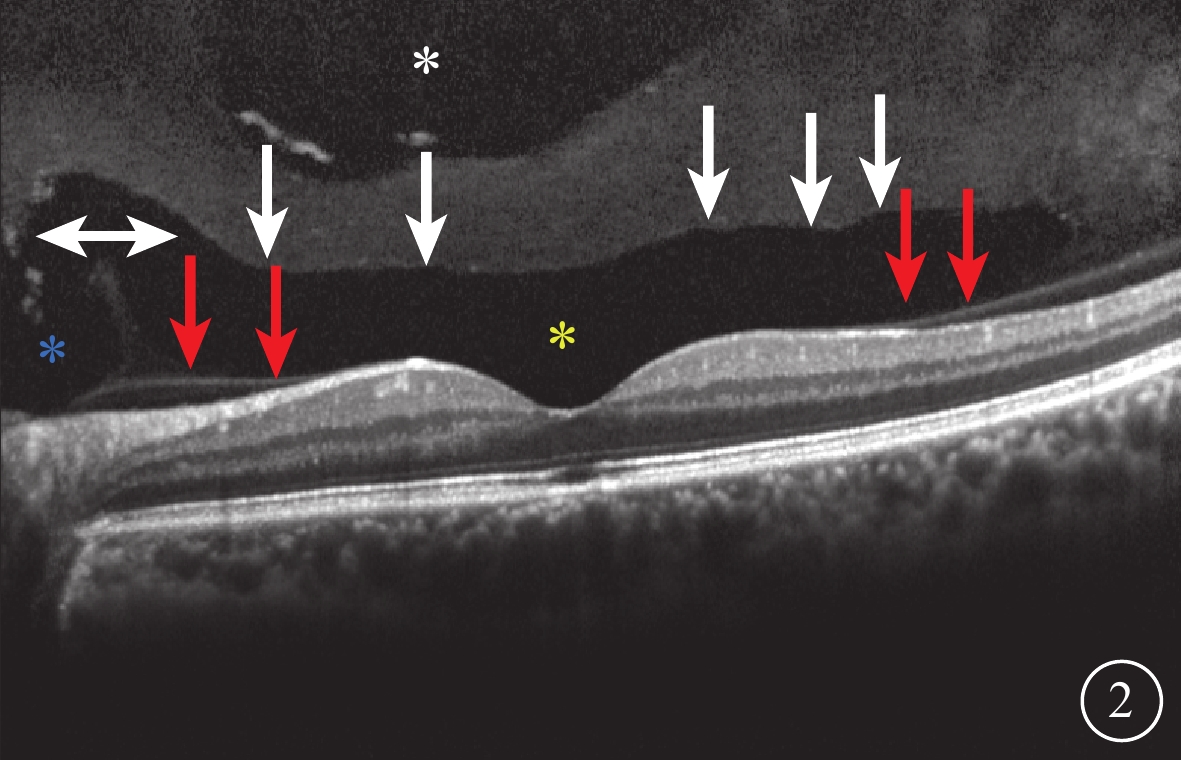

SD-OCT檢查,所有受檢眼常規檢查均未觀察到PPVP。后極部玻璃體掃描模式所采集的圖像可見PPVP結構清晰,表現為黃斑區前弱反射船形腔隙,前界為玻璃體膠原,后界為玻璃體皮質(圖2)。所有受檢眼PPVP鼻側存在一弱反射的無凝膠區域(Martegiani區),兩者之間有一隔膜將其分開。其中,單線掃描可見PPVP與Martegiani區之間存在連接通道(圖2)68只眼(66.0%);多線掃描可見所有受檢眼PPVP與Martegiani區存在連接通道,通道在某些層面出現(圖3)。PPVP前可見一個或多個黃斑上囊(圖2)16只眼(15.5%),其中黃斑上囊與PPVP之間相互連通(圖4)5只眼。PPVP伴玻璃體后脫離(PVD)(圖5)9只眼。采用FDI掃描模式進行檢查的21只眼,視網膜、脈絡膜成像清晰度較好,但玻璃體成像清晰度較差(圖4)。60只眼的PPVP平均最大水平距離為(6 895.7± 872.8)μm,平均垂直距離為(524.1±173.9)μm。

圖2

受檢眼SD-OCT像。黃斑區前船形弱反射區(黃色星),前界為玻璃體凝膠(白箭),后界為玻璃體皮質(紅箭);PPVP鼻側強反射隔膜樣結構將PPVP與Martegiani區(藍色星)隔開,之間有一短通道將兩者連通(白色雙箭);PPVP上方為另一弱反射區域即黃斑上囊(白色星)

圖2

受檢眼SD-OCT像。黃斑區前船形弱反射區(黃色星),前界為玻璃體凝膠(白箭),后界為玻璃體皮質(紅箭);PPVP鼻側強反射隔膜樣結構將PPVP與Martegiani區(藍色星)隔開,之間有一短通道將兩者連通(白色雙箭);PPVP上方為另一弱反射區域即黃斑上囊(白色星)

SD-OCT檢查,所有受檢眼常規檢查均未觀察到PPVP。后極部玻璃體掃描模式所采集的圖像可見PPVP結構清晰,表現為黃斑區前弱反射船形腔隙,前界為玻璃體膠原,后界為玻璃體皮質(圖2)。所有受檢眼PPVP鼻側存在一弱反射的無凝膠區域(Martegiani區),兩者之間有一隔膜將其分開。其中,單線掃描可見PPVP與Martegiani區之間存在連接通道(圖2)68只眼(66.0%);多線掃描可見所有受檢眼PPVP與Martegiani區存在連接通道,通道在某些層面出現(圖3)。PPVP前可見一個或多個黃斑上囊(圖2)16只眼(15.5%),其中黃斑上囊與PPVP之間相互連通(圖4)5只眼。PPVP伴玻璃體后脫離(PVD)(圖5)9只眼。采用FDI掃描模式進行檢查的21只眼,視網膜、脈絡膜成像清晰度較好,但玻璃體成像清晰度較差(圖4)。60只眼的PPVP平均最大水平距離為(6 895.7± 872.8)μm,平均垂直距離為(524.1±173.9)μm。

圖2

受檢眼SD-OCT像。黃斑區前船形弱反射區(黃色星),前界為玻璃體凝膠(白箭),后界為玻璃體皮質(紅箭);PPVP鼻側強反射隔膜樣結構將PPVP與Martegiani區(藍色星)隔開,之間有一短通道將兩者連通(白色雙箭);PPVP上方為另一弱反射區域即黃斑上囊(白色星)

圖2

受檢眼SD-OCT像。黃斑區前船形弱反射區(黃色星),前界為玻璃體凝膠(白箭),后界為玻璃體皮質(紅箭);PPVP鼻側強反射隔膜樣結構將PPVP與Martegiani區(藍色星)隔開,之間有一短通道將兩者連通(白色雙箭);PPVP上方為另一弱反射區域即黃斑上囊(白色星)